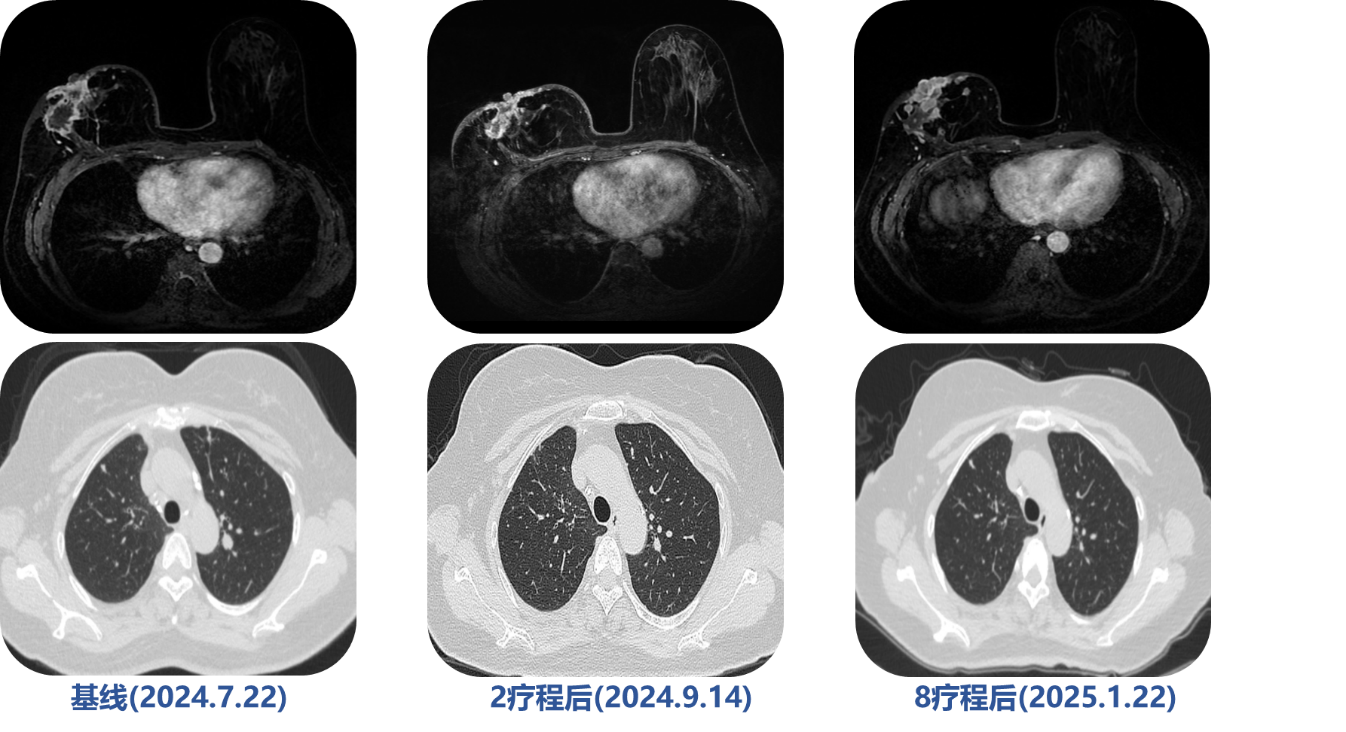

治疗方案:基于PIK3CA突变结果,采用伊那利塞 (9mg qd) + 氟维司群 (500mg q4w)靶向治疗。

疗效评估(2025.7.22):治疗2疗程后,疗效评估为PR 。患者胸壁破溃病灶基本愈合,肺转移灶消失。

最新进展(2025.8.21): 完成3疗程治疗后,胸壁破溃病灶在原有基础上进一步愈合,创面持续改善。目前PFS持续中。